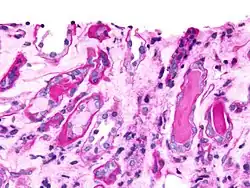

Granular casts

The second-most common type of cast, granular casts can result either from the breakdown of cellular casts or the inclusion of aggregates of plasma proteins (e.g., albumin) or immunoglobulin light chains. Depending on the size of inclusions, they can be classified as fine or coarse, though the distinction has no diagnostic significance. Their appearance is generally more cigar-shaped and of a higher refractive index than hyaline casts. While most often indicative of chronic renal disease, these casts, as with hyaline casts, can also be seen for a short time following strenuous exercise.[4] The "muddy brown cast" seen in acute tubular necrosis is a type of granular cast.